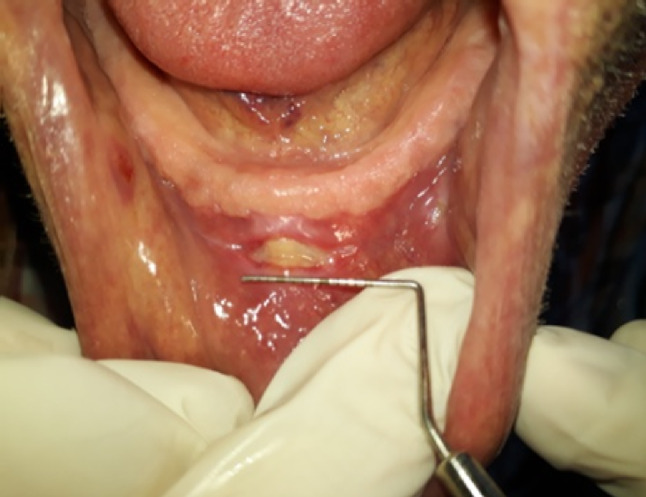

本研究对60例患者进行了研究,并对120个全口义齿进行了检查,以确定全口义齿交付后创伤性溃疡的位置和频率,并在随访期间评估其愈合过程。所有患者在假牙交付后一周进行调整预约。使用定制设计的格式记录溃疡的位置,并在每次就诊期间测量其大小,直到完全愈合。结果显示,溃疡大小最显著的减少发生在第一次调整访问之后。下颌义齿损伤明显多于上颌义齿损伤。在义齿相关损伤方面,男女无显著差异。事实证明,定期调整是减少溃疡大小的主要因素,消除了对额外治疗材料的需要。

This study was conducted on 60 patients, and a number of 120 complete dentures were examined to determine the location and frequency of traumatic ulcerations following the delivery of complete dentures and to evaluate their healing process during follow-up appointments. All patients had adjustment appointments scheduled one week after denture delivery. The ulcers' locations were recorded using a custom-designed format, and their sizes were measured during each visit until complete healing. The results showed that the most significant reduction in ulcer size occurred after the first adjustment visit. Injuries related to mandibular dentures were significantly more common than those related to maxillary dentures. There was no significant difference in denture-related injuries between males and females. Regular adjustments proved to be the primary factor contributing to ulcer size reduction, eliminating the need for additional therapeutic materials.